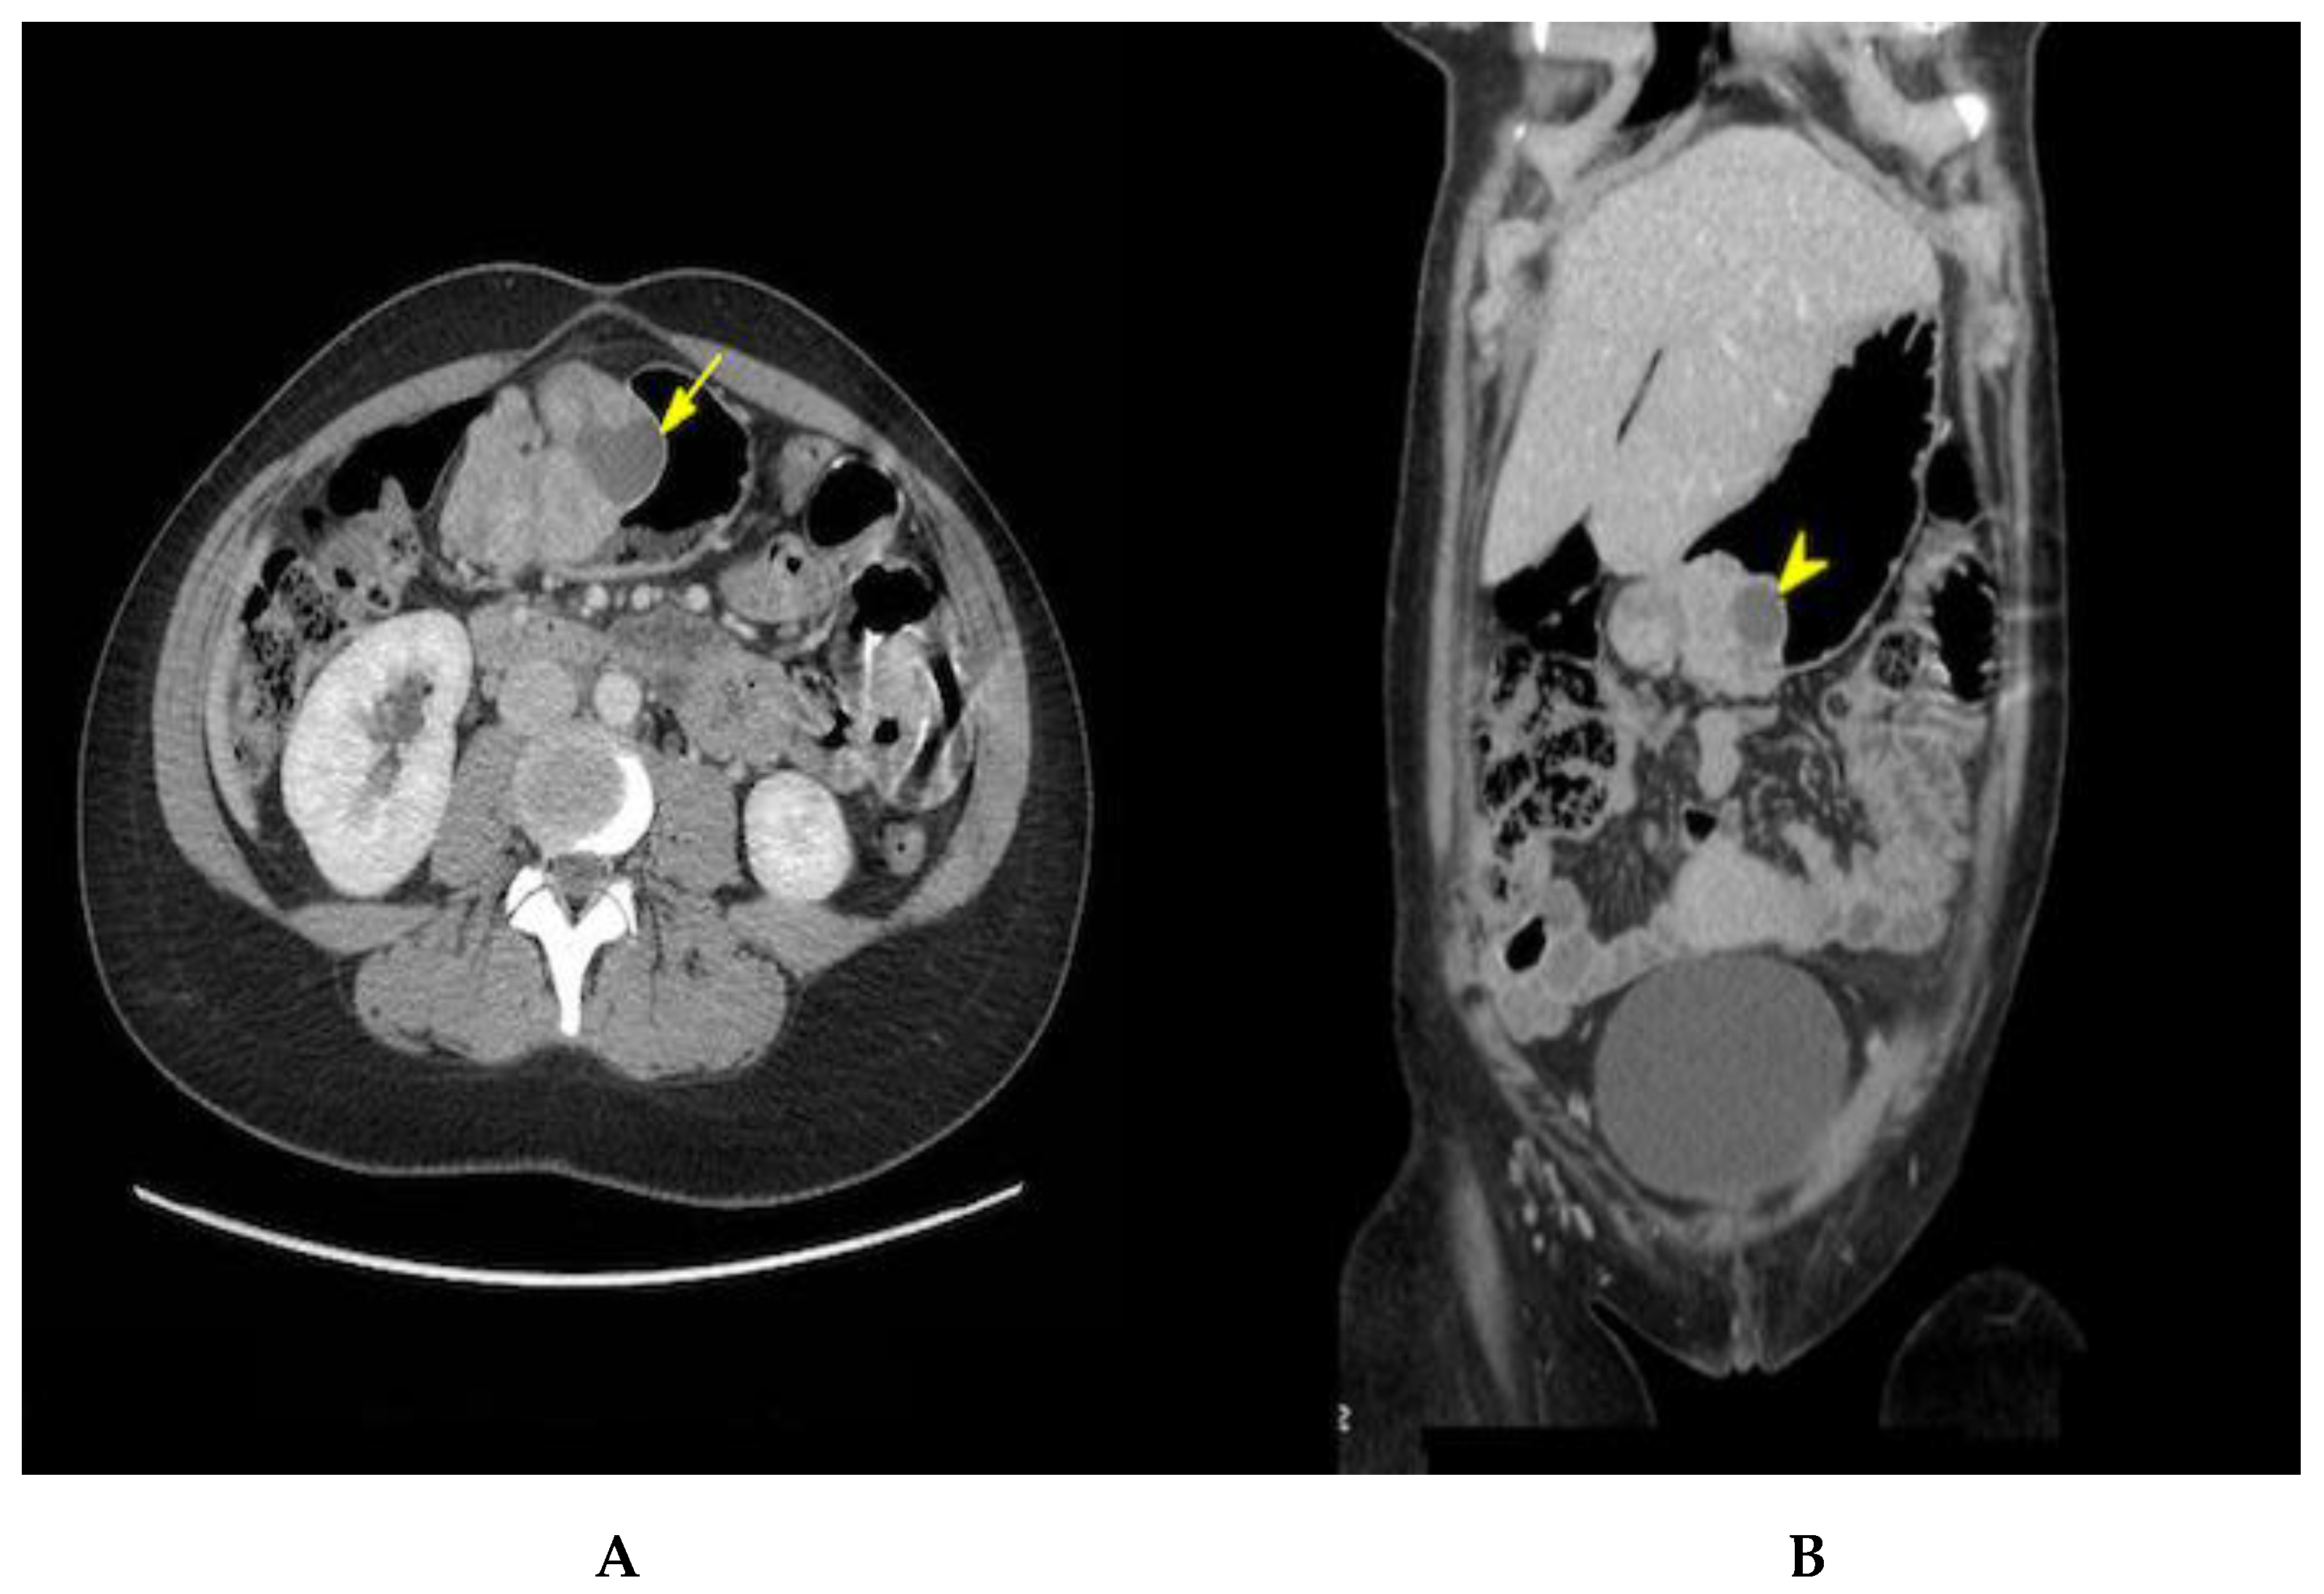

2. Case Presentation